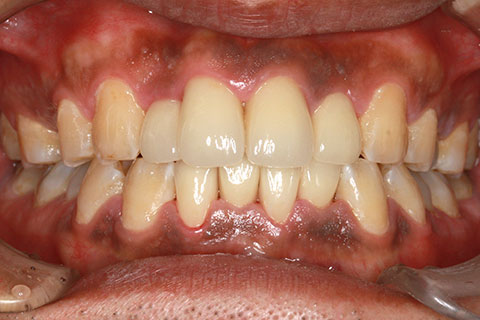

• 症例2

治療前

インプラント埋入時

治療後

年齢・性別

57歳男性

治療期間

3ヶ月

抜歯

なし

治療費

154万円

備考

左上5.6.7 及び左下6.7欠損

治療内容

左上5.6.7と左下6.7欠損部にインプラント埋入

施術の副作用(リスク)

オペによる知覚障害。インプラントによる歯肉炎。インプラント脱落。